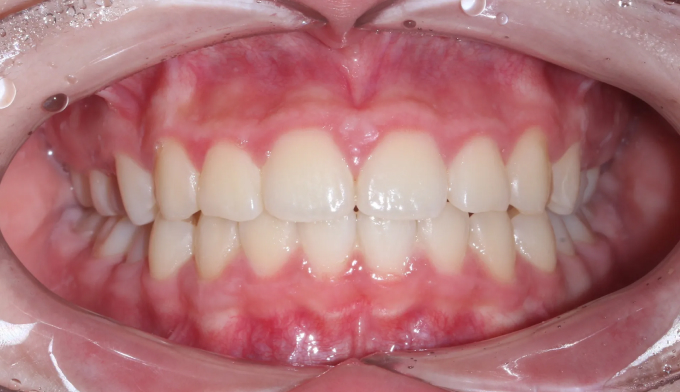

위 작은어금니가 겹쳐져서 맹출하였습니다.

공간이 부족하므로 먼저 양쪽으로 치아를 벌려 공간을 확보해준 후 겹쳐진 치아들을 배열해줍니다.

치아 배열 중 앞니가 뻐드러지지 않게 조심합니다.

총 치료기간은 20개월입니다.